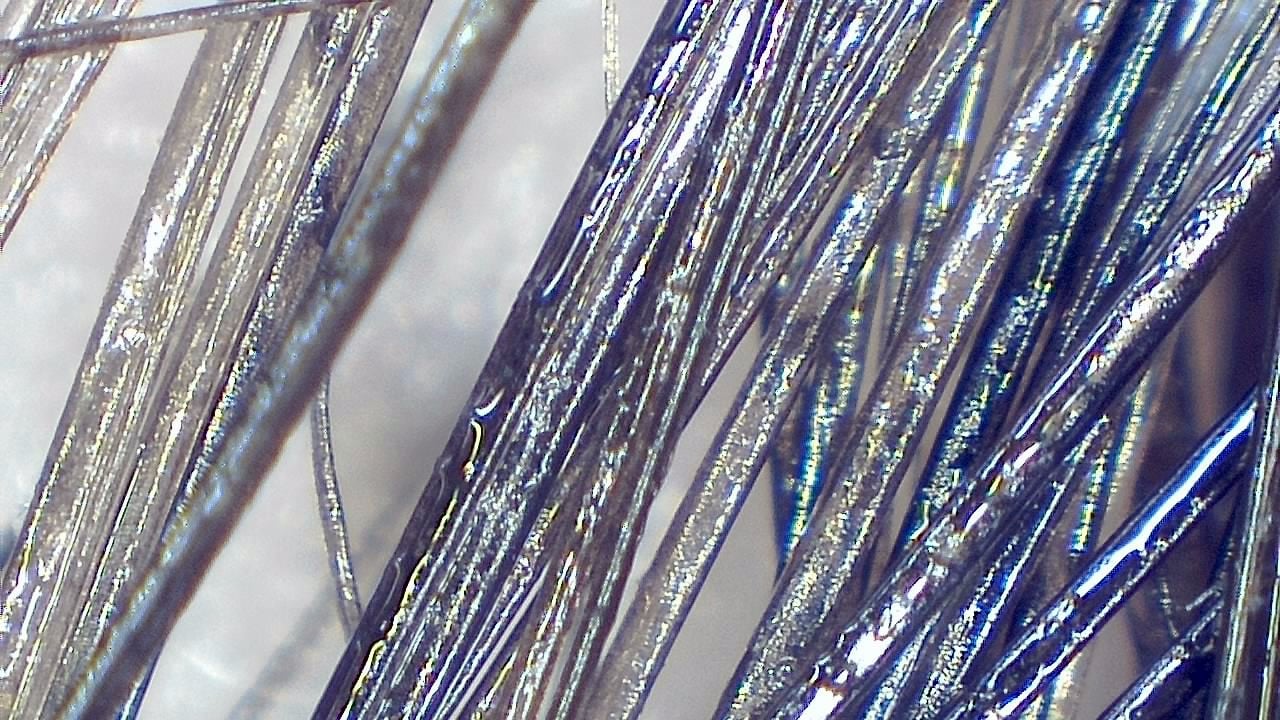

Portable magnified viewing for scalp surface, hair shafts, follicular openings, and visual documentation over time.

Trichoscopy is a non-invasive visual examination technique used by trained professionals to observe the scalp surface and hair shafts. Smart G-Scope provides a portable USB workflow for magnified viewing and image capture.

The device can support documentation of hair shaft appearance, scalp surface features, follicular openings, and visible changes over time. It is most useful when images are captured under consistent lighting and positioning.

What you can observe

- Hair shafts and visible shaft diameter variation.

- Magnified viewing of hair shafts, scalp surface, and visible follicular openings.